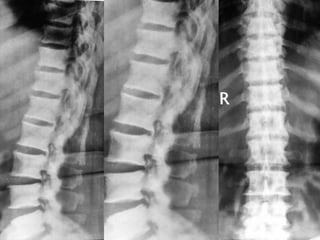

• X-ray of Chest.

• X- Both fore arms - AP

• MRI of Dorsal and Lumbar Spine.

Case report –cont…. • X-ray of Chest. • X- Both fore arms - AP • MRI of Dorsal and Lumbar Spine. • CBC, serum Creatinine, TSH, PTH, Ca, Alk Po4, Urine routine.